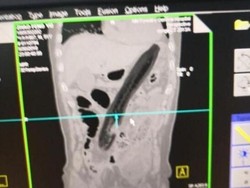

Diyakini untuk Usir Setan, 10 Batang Jarum Ditemukan di Tubuh Seorang Bayi

Malang betul bayi laki-laki berusia 9 bulan di Tajikistan ini. Sebanyak 10 jarum ditemukan di dalam tubuhnya, diyakini berasal dari ritual untuk mengusir setan.